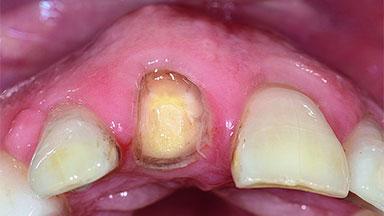

Replacement of an Upper Right Central Incisor with Root Resorption: Ridge Preservation, Early Placement of an RC Bone Level Implant

A 49-year-old female patient was referred for implant therapy to replace the upper right central incisor (tooth 11). The tooth had been assessed by an endodontist who diagnosed a vertical fracture of the root. The tooth had a hopeless prognosis and needed to be extracted. The patient was healthy and was not taking any medications. She was allergic to penicillin. The patient had high esthetic demands but her expectations were realistic. The extraoral examination revealed no facial asymmetries. The right temporomandibular joint demonstrated an opening click but was otherwise asymptomatic. The lip line was high with a significant gingival display.

Bone Volume Horizontally and vertically sufficient Horizontally deficient Deficient vertically or deficient vertically AND horizontally

Bone Volume Deficient vertically or deficient vertically AND horizontally